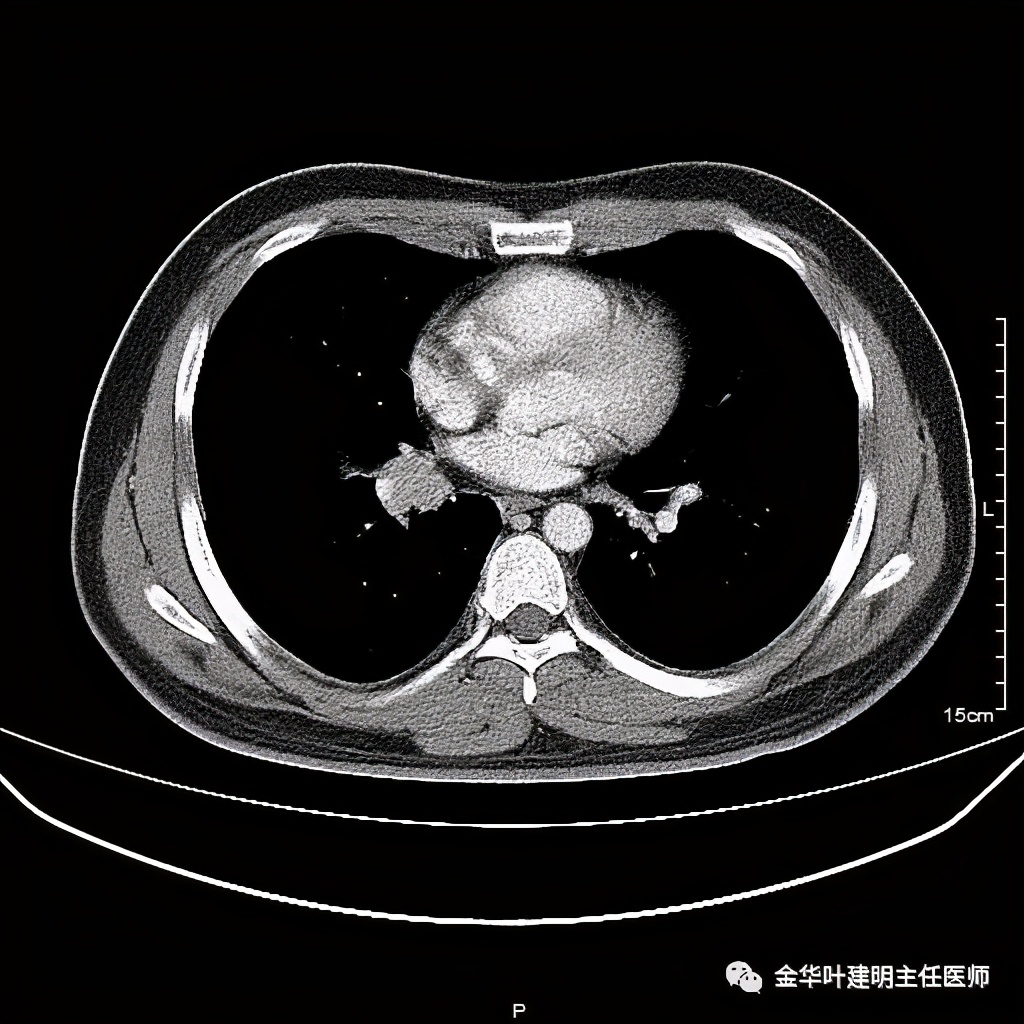

五、浸润性腺癌之粘液腺癌:

影像特征:这个病例是我在术前仅凭影像就判断其为粘液腺癌,术后确诊的。粘液腺癌表现为 实性乏收缩力、密度较均匀 的实性结节。病灶的边界一般非常清楚,没有毛刺、磨玻璃、卫星灶等,但又乏收缩力,像本例紧贴胸膜也不会有牵拉凹陷;同时病灶的密度又比较均匀(粘液成份)。良性肿瘤密度要更高些、慢性炎没有这么光整的边界,也容易有瘢痕收缩方面的影像表现、其他实性的腺癌则要有收缩力、腺泡型虽然也缺乏收缩力,但密度要不均匀些。